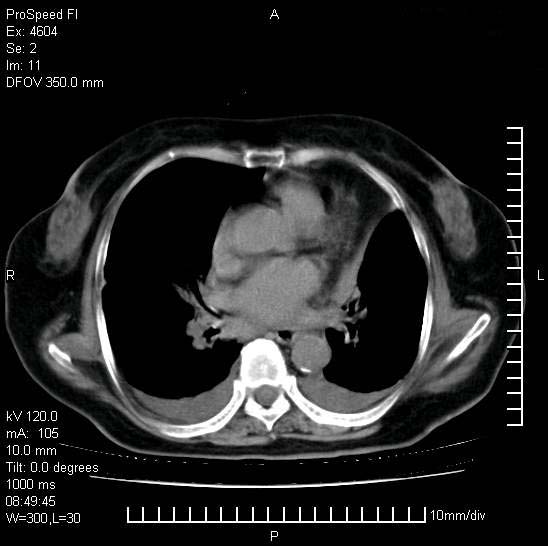

十几年前曾患肺结核,一周前突咳血约100ml,中性粒细胞稍高,诊断两上肺陈旧结核,下肺炎症,给予抗炎治疗,近几日晚上高热,39度,仍咳少量血,4天前ct及今天ct上传。

[face=黑体]8月30日[/face]

今天ct

支持陈旧性肺结核并两下肺感染,两侧胸腔积液。

短短几天内,病变范围明显增多扩大,以左侧明显,而且双侧出现胸水,还是考虑感染.

短短几天内,病变范围明显增多扩大,以左侧明显,而且双侧出现胸水,我更多考虑左侧中心性肺癌并并阻塞性不张及肺炎,炎症变化也太快了!

1)两肺结核并感染。2)不排除左肺上叶中央型肺癌并阻塞性肺炎、肺不张可能;建议行纤支镜检查。3)右肺门及纵隔淋巴结肿大。4)双侧胸腔积液。